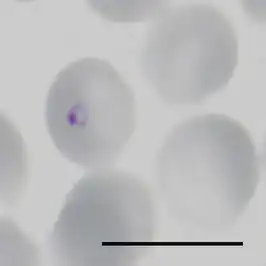

| Ringstadium van Plasmodium falciparum in een geïnfecteerde erytrocyt. Het zwarte streepje is 10 μm lang. | |||||||||||||